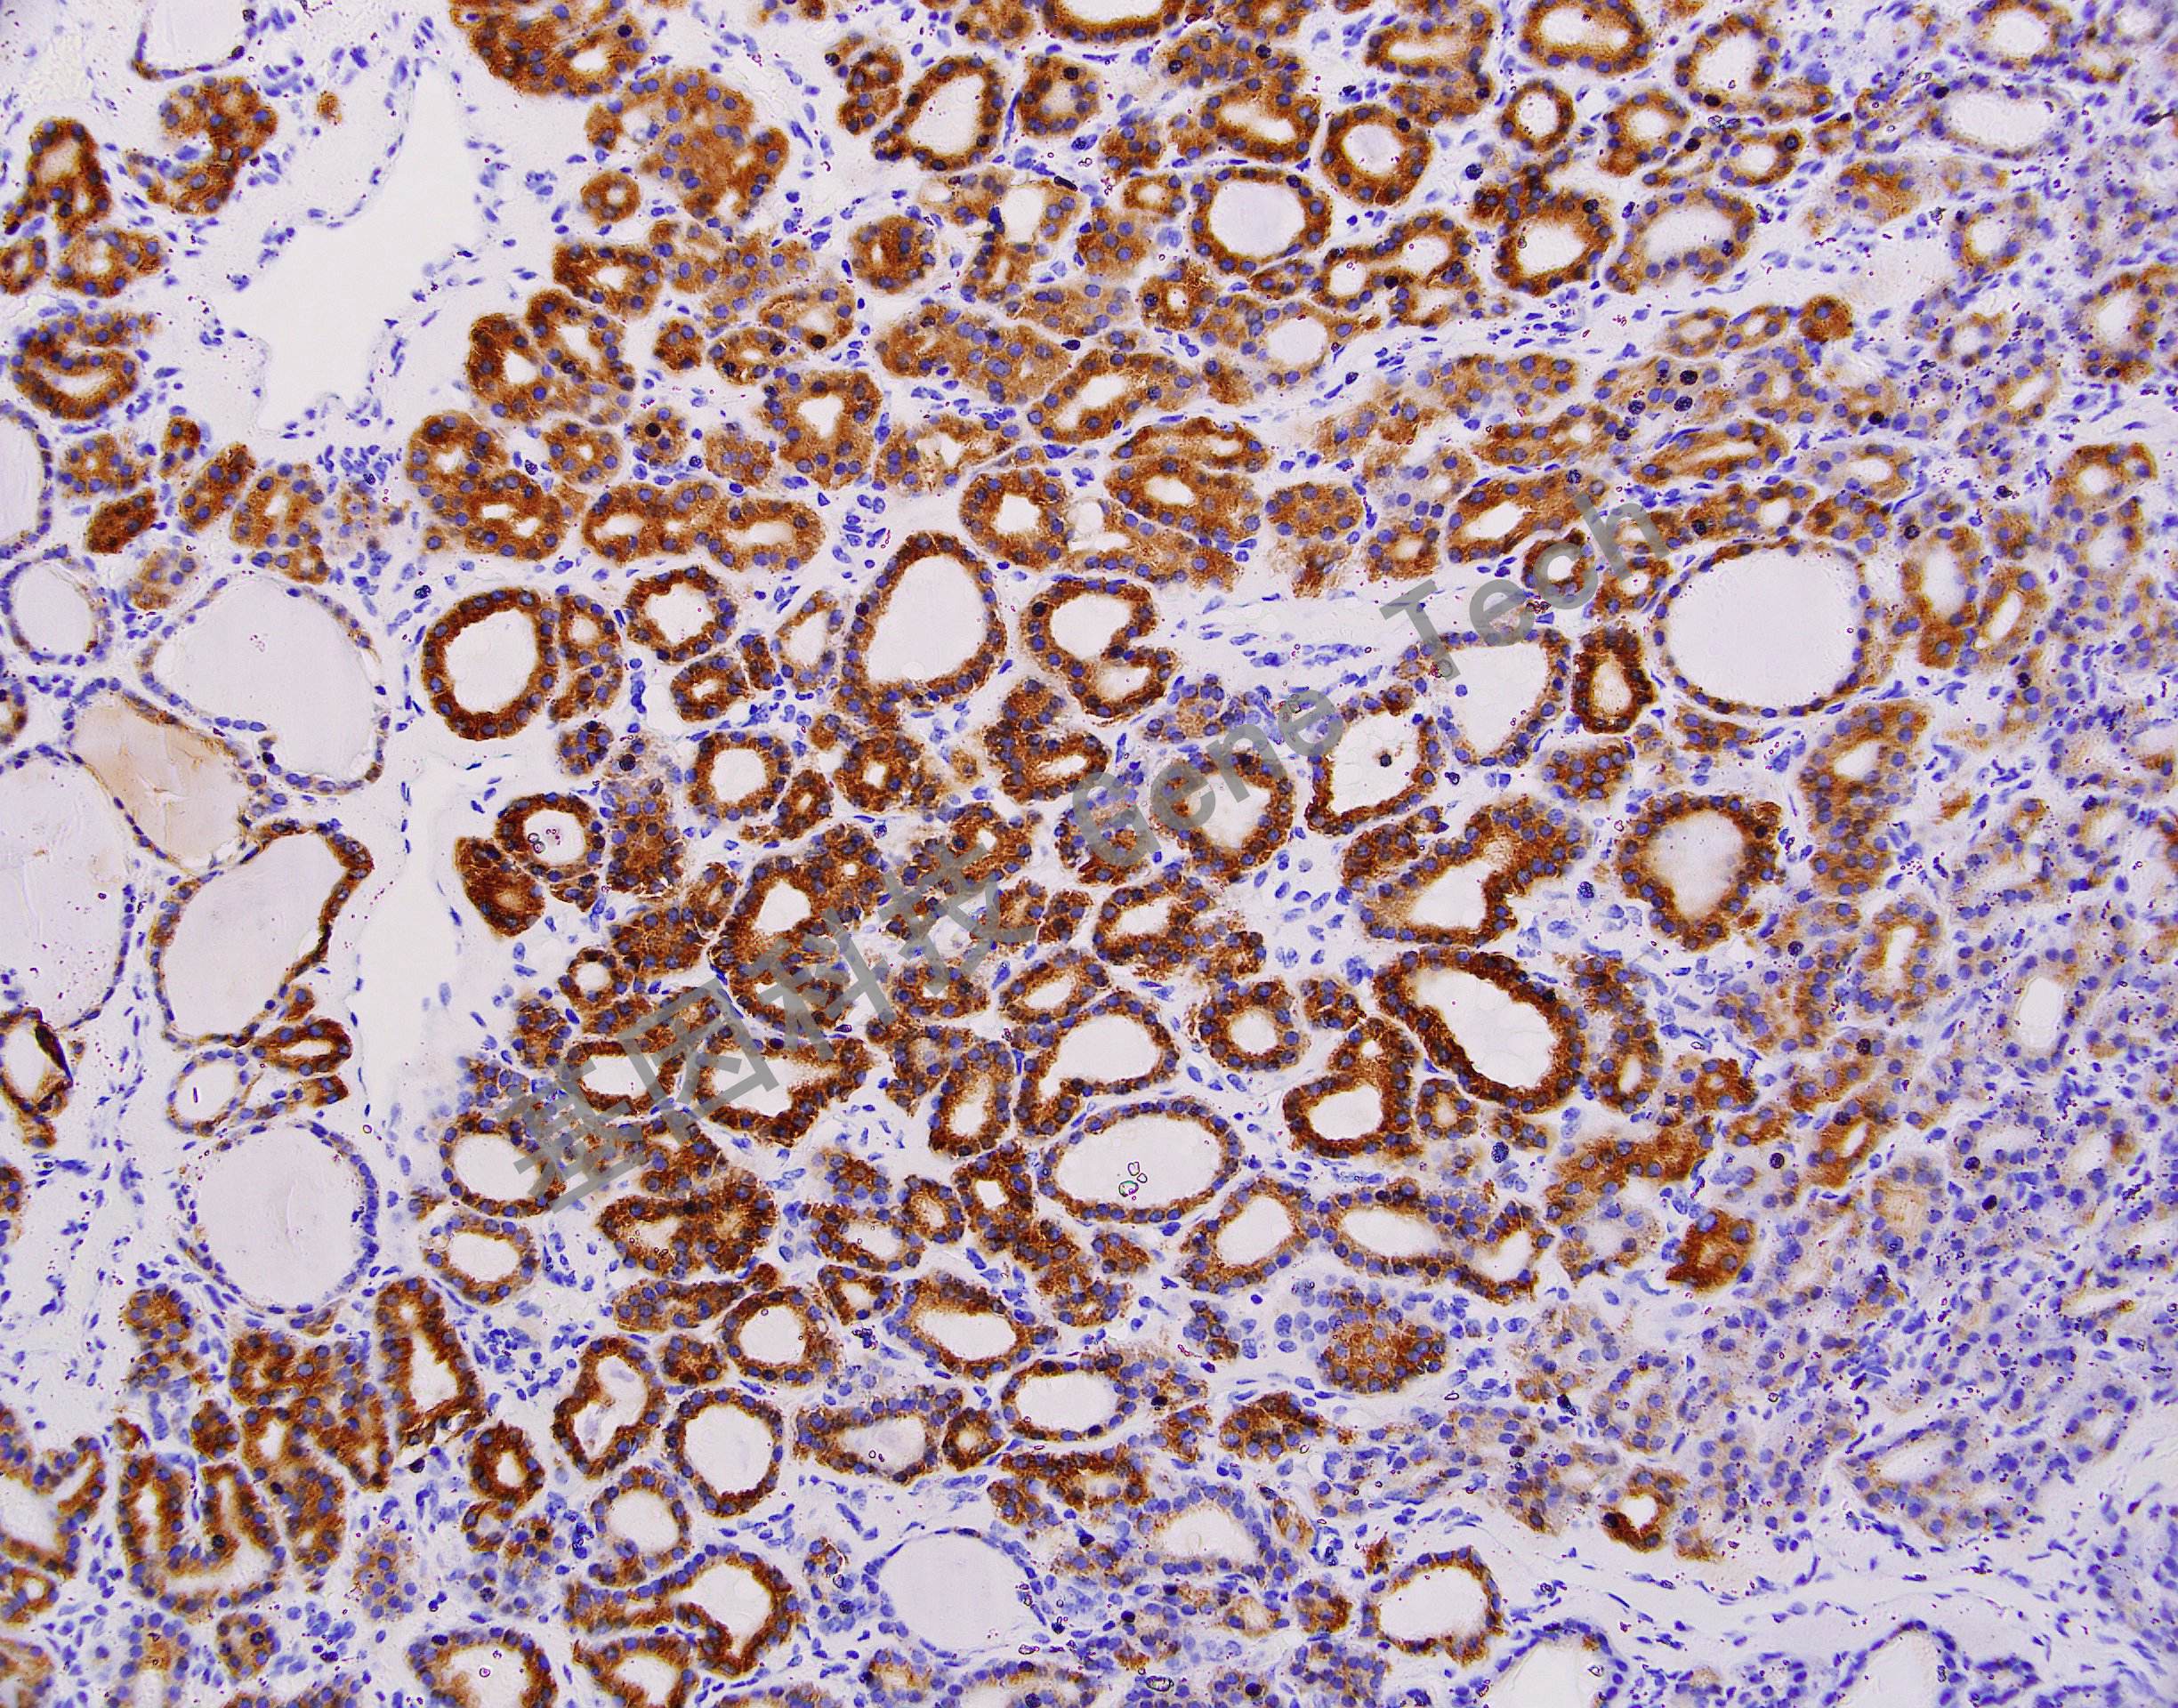

| 克隆號(hào):AC25 | 種屬:鼠 | 適用染色系統(tǒng):GTvisionTM |

| 預(yù)處理:高pH熱修復(fù) | 陽(yáng)性部位:細(xì)胞漿 | 陽(yáng)性對(duì)照:甲狀腺 |

| 簡(jiǎn)介:TPO(Thyroid peroxidase, 甲狀腺過(guò)氧化物酶)由甲狀腺濾泡細(xì)胞合成,位于甲狀腺上皮細(xì)胞的頂端游離面上,直接參與甲狀腺細(xì)胞中碘的氧化,酪氨酸的碘化及碘化酪氨酸的偶聯(lián)等,它是甲狀腺激素合成過(guò)程中的關(guān)鍵酶。在正常、增生性及絕大多數(shù)良性腫瘤性甲狀腺組織中高度表達(dá),在甲狀腺惡性腫瘤中TPO表達(dá)明顯減少。該抗體主要用于甲狀腺組織良、惡性腫瘤的鑒別診斷。 | ||

| 甲狀腺癌石蠟切片,用 TPO(GT2167)染色,細(xì)胞漿陽(yáng)性,DAB 顯色。 | ||